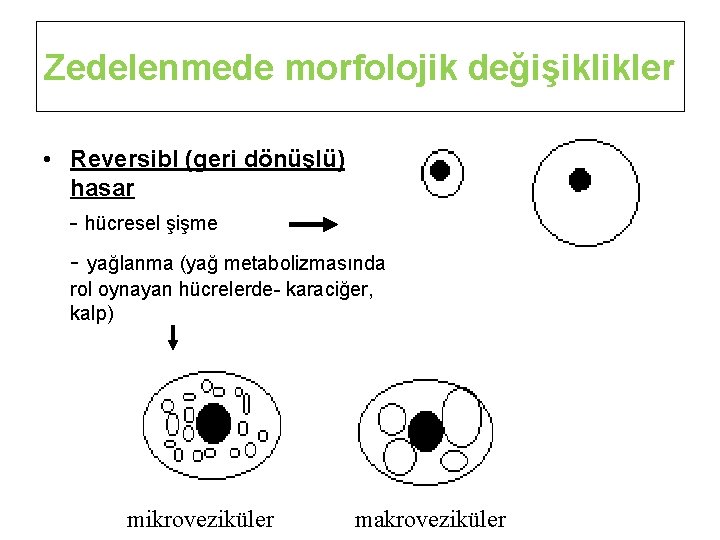

Zedelenmede morfolojik değişiklikler • Reversibl (geri dönüşlü) hasar - hücresel şişme - yağlanma (yağ metabolizmasında rol oynayan hücrelerde- karaciğer, kalp) mikroveziküler makroveziküler